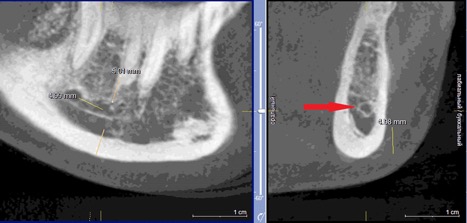

При измерении расстояния от резцовой петли до вестибулярной стенки нижней челюсти и её топографии в области правила «трёх пятёрок», выделено три положения канала, в котором проходит резцовая петля: канал прилежит, т.е. стенка канала образована кортикальной частью (рис 3), касается, т.е. имеет одну общую точку (рис 4) и не имеет общих точек.

Рисунок 4. КЛКТ Сагиттальныи и коронарныи реформаты переднего отдела нижнеи челюсти..jpg

Рисунок 4. КЛКТ Сагиттальный и коронарный реформаты переднего отдела нижней челюсти.

Канал соприкасается с кортикальной частью кости (красная стрелка – резцовая петля).